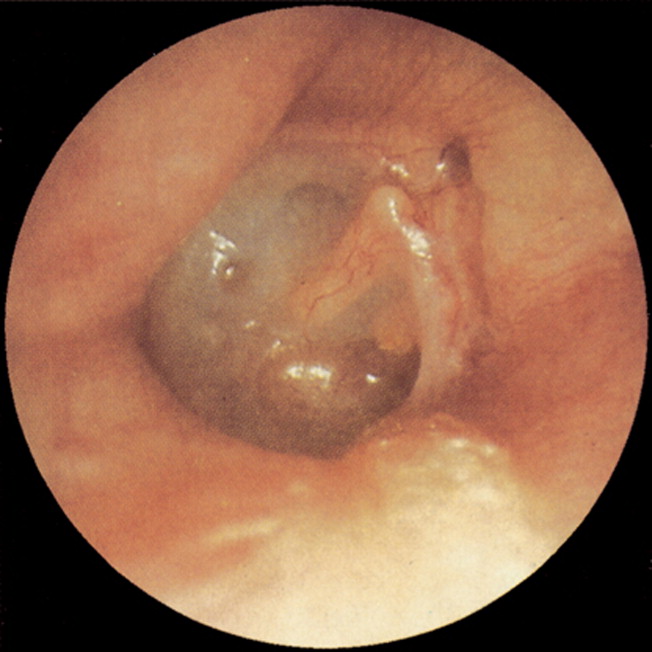

Una característica común de la infección crónica del oído medio es la presencia de perforación o retracción de la membrana timpánica. Estos cambios en la membrana timpánica pueden facilitar la entrada de bacterias y otros patógenos en el oído medio, lo que contribuye a la persistencia de la infección.

Los hallazgos clínicos de la otitis media crónica se caracterizan principalmente por la presencia de secreción purulenta del oído, que es el rasgo distintivo de esta condición. Esta descarga puede ser continua o intermitente, con una mayor severidad durante las infecciones del tracto respiratorio superior o después de la exposición al agua. Esta secreción purulenta puede variar en cantidad y consistencia, y generalmente es indicativa de una infección bacteriana persistente en el oído medio.

La pérdida de audición conductiva es otra manifestación común de la otitis media crónica. Esto ocurre como resultado de la destrucción de la membrana timpánica o de la cadena osicular, o de ambos. La membrana timpánica y los huesecillos del oído medio, como el martillo, el yunque y el estribo, forman parte del sistema de conducción del sonido en el oído medio. Cuando estos componentes se ven afectados por la infección crónica, se produce una pérdida de audición conductiva debido a la interrupción en la transmisión del sonido desde el oído externo hasta el oído interno.

La destrucción de la membrana timpánica o de la cadena osicular puede ser el resultado de la inflamación crónica y la presión generada por la acumulación de líquido y pus en el oído medio. Esta pérdida de audición conductiva puede ser leve a moderada y puede afectar la capacidad del individuo para escuchar claramente los sonidos o entender el habla.